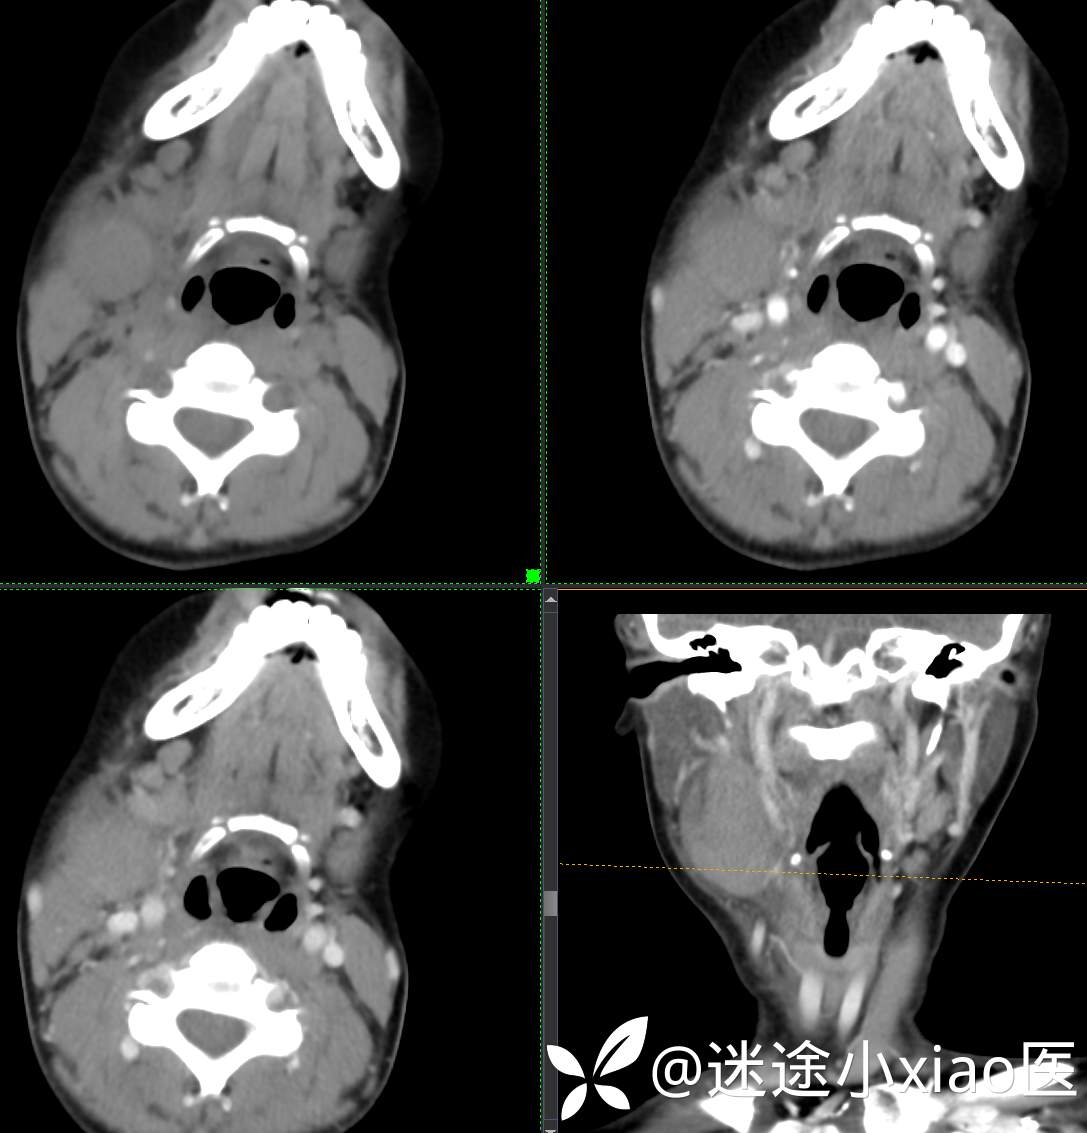

头颈组16:青少年女性,发现右颈部肿物半月余,感染?肿瘤?

现病史:患者半月余前无明显诱因下发现右颈部肿物,大小4.2*2.1cm,局部无红肿,皮温正常,有压痛,感头晕头痛,无其他不适。查甲状腺及颈部淋巴结B超提示:双侧甲状腺多发结节;右侧多发肿大淋巴结。初步诊断为“淋巴炎”,予“头孢类”抗生素抗感染治疗12天(具体药物不详),自觉肿块胀痛缓解,头晕头痛症状仍存。